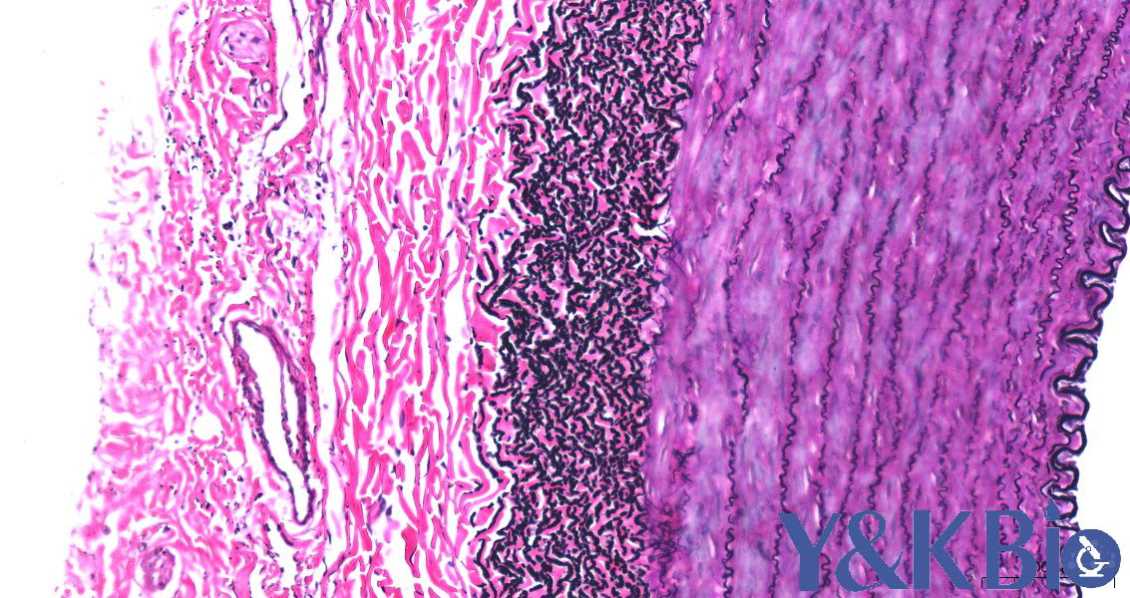

四、EVG染色

适用于血管、皮肤、肺 吉林石蜡切片 ,观察弹力纤维、胶原纤维

染色结果: 弹力纤维呈紫黑色,胶原纤维呈红色,其它呈黄色